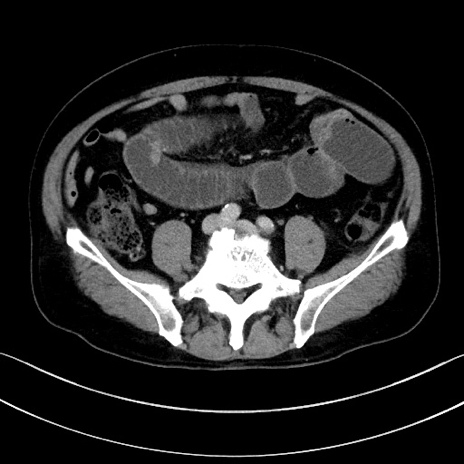

冠状断像

症例15(横断像)

【症例】70歳代男性

【主訴】腹痛

【現病歴】今朝から腹痛あり。全体的に痛い。特に左上の方。排ガスが今日はない。冷や汗が出る。

【既往歴】直腸癌術後

【身体所見】左側腹部〜上腹部に圧痛あり。腹膜刺激症状明らかなではない。軽度反跳痛。左下腹部に術後瘢痕あり。

【データ】WBC 7700、CRP 0.02